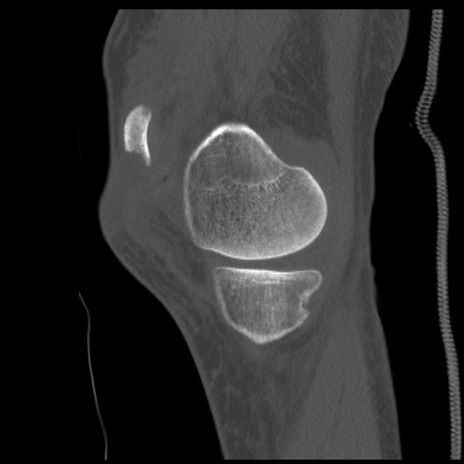

症例28 右膝関節CT(矢状断像)

右膝関節CT